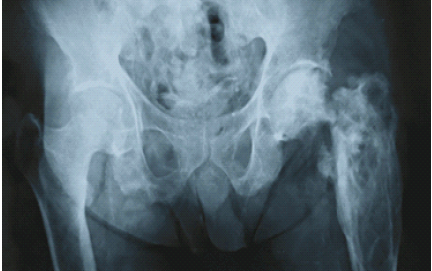

A 63-year-old male patient presented with pain in the left hip. An X-ray showed an expansile lytic lesion on the proximal femur, and later on, the neck of the femur fractured, and hemiarthroplasty was done before the parathyroidectomy. The patient died before the parathyroidectomy (Fig. 5).

Figure 5: A 63-year-old male patient presented with pain in the left hip. X-ray showed an expansile lytic lesion on the proximal femur, and later on, the neck of the femur fractured.